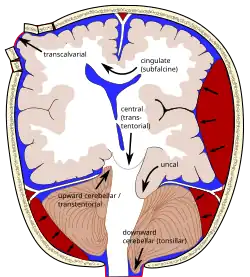

The most common presentation of cerebrovascular diseases is an acute stroke, which occurs when blood supply to the brain is compromised.[13] Symptoms of stroke are usually rapid in onset, and may include weakness of one side of the face or body, numbness on one side of the face or body, inability to produce or understand speech, vision changes, and balance difficulties.[1] Hemorrhagic strokes can present with a very severe, sudden headache associated with vomiting, neck stiffness, and decreased consciousness.[13] Symptoms vary depending on the location and the size of the area of involvement of the stroke. Edema, or swelling, of the brain may occur which increases intracranial pressure and may result in brain herniation. A stroke may result in coma or death if it involves key areas of the brain.[14]